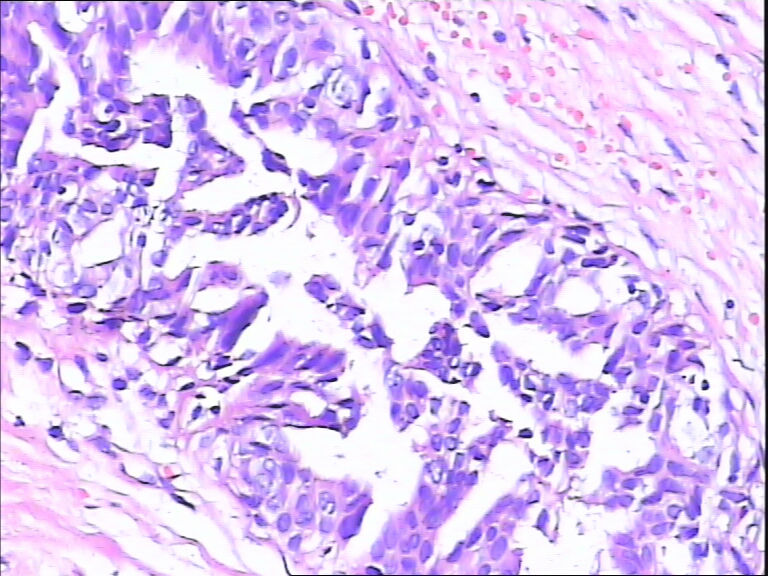

B3862乳腺包块

40岁,发现乳腺包快5月

标签:UDH ADH

觉得像UDH,做CK5,P63,UDH CK5腺上皮阳性,ADH CK5腺上皮阴性

ADH

DIN1b

导管不典型增生,不够导管内癌,做一做免疫组化就一目了然了

感觉不是普通型增生(UDH),应该到ADH或DCIS  免疫组化 ck5/6  34bE12

导管内癌

觉得不够癌

考虑导管内原位癌  需做组化确诊

Quality of the slides is not good.

More like UDH